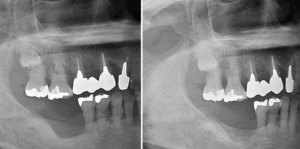

フラップ手術は、進行した中等度~重度の歯周病に対して行う「外科的な治療法」です。 歯ぐきの奥深くに潜んでいる歯石や歯垢(プラーク)を直接見える状態にして、徹底的にキレイにする方法です。

フラップ手術とは、進行した歯周病に対して行う外科的な治療方法のひとつです。

通常の歯石取り(スケーリング)や歯ぐきの中の清掃(SRP)では届かない「歯の根の奥深く」に歯石や歯垢が入り込んでいる場合、そのままでは完全に取り除くことができません。

そこで、歯ぐきを一部開いて(これを「フラップ」といいます)、目で確認しながら感染した部分の歯石や汚れを直接取り除くのが「フラップ手術」です。

歯ぐきをめくって根の表面をきれいにし、歯槽骨(しそうこつ=歯を支える骨)の状態も確認しながら、感染部分を徹底的に除去します。 処置のあとは、歯ぐきを元に戻して縫合します。